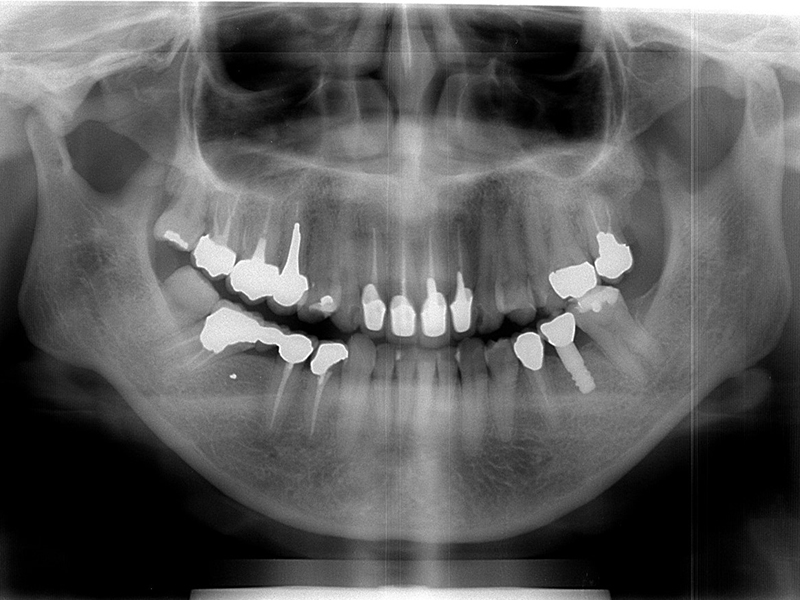

初診